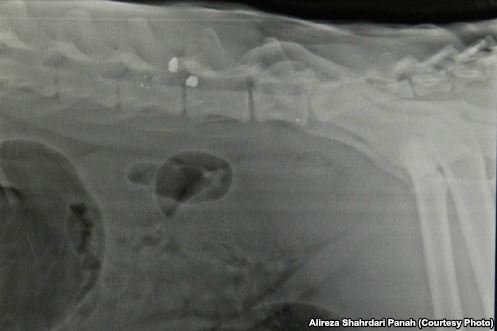

تعداد زیادی گلوله و ساچمه، قطع دست در تله

ایمان معماریان درباره وضعیت پلنگ وقتی به تهران رسید میگوید: «وقتی حیوان به تهران رسید، در قفسی بسیار نامناسب بود. بعد از بیهوشی و انجام رادیوگرافی مشخص شد که تعداد بسیار زیادی گلوله در بدن حیوان وجود دارد که به زمانهای مختلف بازمیگردند.»

وی میافزاید: «همچنین دست راست حیوان به دلیل گیر گردن در تله مدتها پیش از ناحیه مچ قطع شده است. یکی از گلولههایی که به تازگی به حیوان شلیک شده بود کاملا در مجاورت مهره ششم کمری در کانال نخاعی دیده میشد. سی تی اسکن نیز نشان داد که گلوله از بدنه مهره پنجم کمری وارد کانال نخاعی شده و تا انتهای مهره ششم در کانال نخاعی حرکت کرده و کل کانال را پرکرده است.»

عکس رادیولوژی، تیراندازی و آسیب های کمر حیوان را نشان می دهد